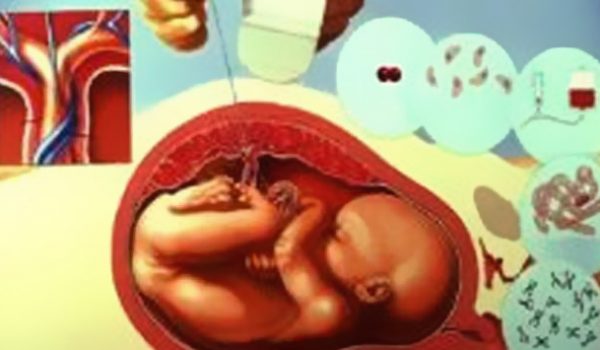

medicina-fetal

Medicina Fetal

O intuito da Medicina Fetal é de diagnosticar, tratar e até prevenir as patologias fetais, hoje considerada uma especialidade multidisciplinar e de grande importância. Saiba Mais…